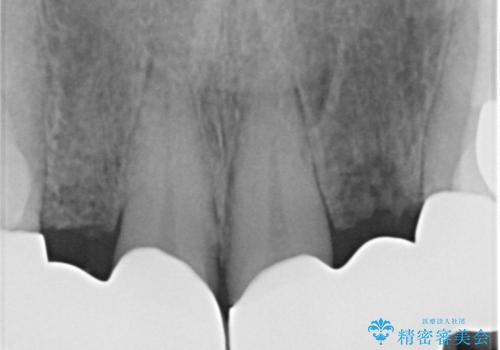

- 前歯のがたつきが気になるとの事で来院。

②の方を選択されましたので被せ物治療を行いました。

また、左上の犬歯の根の再治療も行いました。

最終的な被せ物は抜歯を行なってから半年経ってから形を整えて型取りを行います。